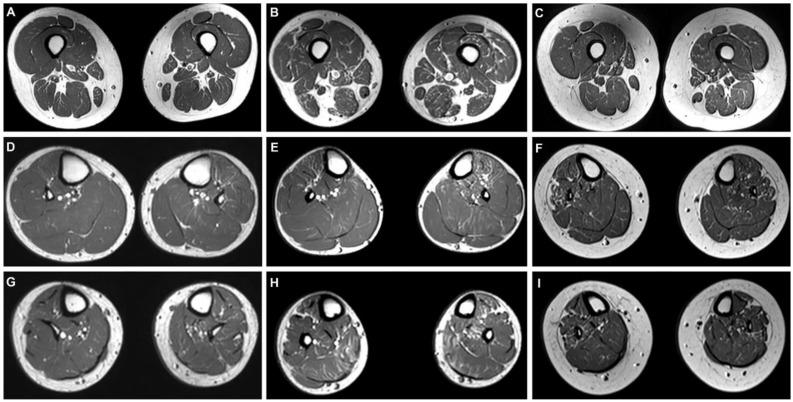

Charcot-Marie-Tooth disease (CMT) is the most common inherited peripheral neuropathy. Mutations in the gene cause dominant intermediate CMT type F (CMTDIF). The aim of this study is to investigate phenotypic heterogeneities and characteristics of CMT patients with mutations. We enrolled 1143 Korean CMT families and excluded 344 families with a duplication. We further analyzed the 799 remaining families to find their mutations using whole-exome sequencing (WES). We identified two mutations (p.Gly77Arg and p.Lys89Glu) in three families, among which a heterozygous p.Gly77Arg mutation was novel. In addition, a significant uncertain variant (p.Thr177Asn) was observed in one family. The frequency of the mutation in the Korean population is 0.38% in duplication-negative families. All three families showed mutation. Electrophysiological findings regarding the p.Lys89Glu mutation showed that the motor nerve conduction velocity (MNCV) of the median nerve was markedly reduced, indicating demyelinating neuropathy, and sural nerve biopsy revealed severe loss of myelinated axons with onion bulb formation. Lower extremity Magnetic Resonance Imaging (MRI) demonstrated relatively more severe intramuscular fat infiltrations in demyelinating type (p.Lys89Glu mutation) patients compared to intermediate type (p.Gly77Arg mutation) patients. The anterolateral and superficial posterior compartment muscles of the distal calf were preferentially affected in demyelinating type patients. Therefore, it seems that the investigated mutations do cause not only the known intermediate type but also demyelinating-type neuropathy. We first presented three Korean families with mutations and found phenotypic heterogeneities of both intermediate and demyelinating neuropathy. We suggest that those findings are useful for the differential diagnosis of CMT patients with unknown variants.

夏科-马里-图思病(CMT)是最常见的遗传性周围神经病。该基因的突变导致显性中间型CMT F型(CMTDIF)。本研究的目的是调查携带该突变的CMT患者的表型异质性和特征。我们纳入了1143个韩国CMT家系,并排除了344个存在该基因重复的家系。我们进一步分析了剩下的799个家系,通过全外显子组测序(WES)来寻找它们的该基因突变。我们在三个家系中鉴定出两个突变(p.Gly77Arg和p.Lys89Glu),其中杂合的p.Gly77Arg突变是新发现的。此外,在一个家系中观察到一个显著的不确定变异(p.Thr177Asn)。在无该基因重复的韩国人群中,该基因突变的频率为0.38%。所有三个家系均显示有该基因突变。关于p.Lys89Glu突变的电生理结果显示,正中神经的运动神经传导速度(MNCV)明显降低,提示脱髓鞘性神经病,腓肠神经活检显示有髓轴突严重丢失并伴有洋葱球形成。下肢磁共振成像(MRI)显示脱髓鞘型(p.Lys89Glu突变)患者的肌内脂肪浸润比中间型(p.Gly77Arg突变)患者相对更严重。脱髓鞘型患者小腿远端的前外侧和后浅肌群优先受累。因此,似乎所研究的该基因突变不仅会导致已知的中间型,还会导致脱髓鞘型神经病。我们首次报道了三个携带该基因突变的韩国家系,并发现了中间型和脱髓鞘性神经病的表型异质性。我们认为这些发现有助于对具有未知该基因变异的CMT患者进行鉴别诊断。